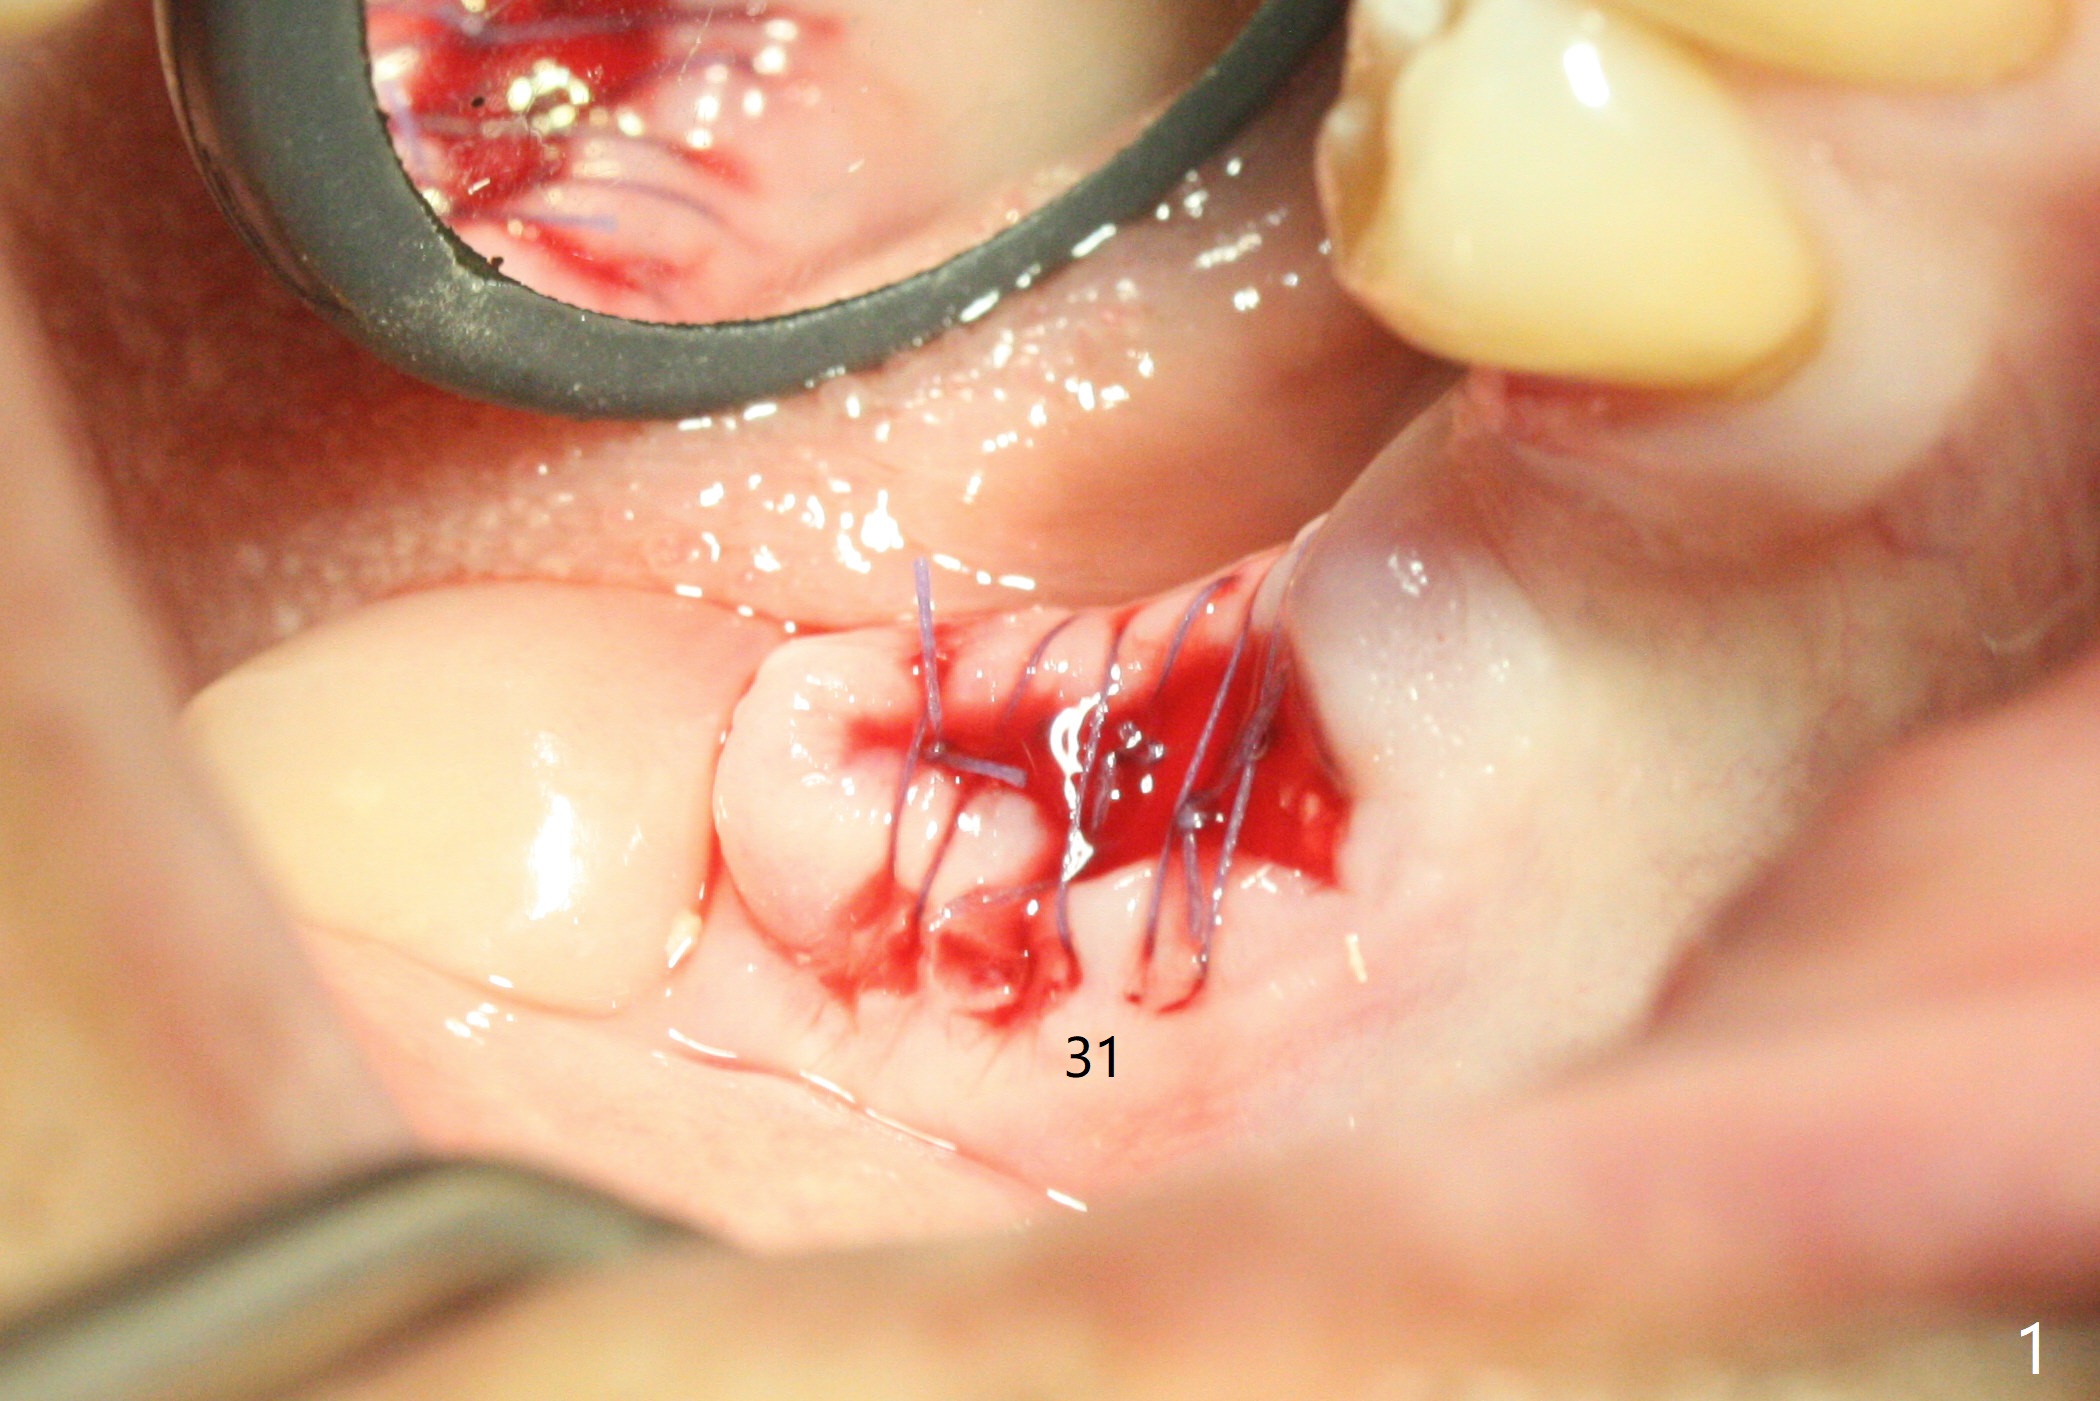

Since the tooth #31 is mesially shifted and tilted with mobility, it would not be a good distal anchor tooth for #30 implant placement with a surgical guide. It is extracted when an implant is placed at #3 so that autogenous bone harvested from the osteotomy at #3 will be mixed with allograft (Vanilla) and alloplast (Osteogen) for #31 socket preservation (Fig.3 M). After Osteogen plug and 6-month membrane are placed over the mixed graft, the socket is approximated with 5-0 PGA (Fig.1,2). The 6-month membrane appears to be retained 5 days postop (Fig.4). The socket reduces substantially nearly 1 month postop (Fig.5,6). The small 2nd molar socket (as compared to the 1st molar one) heals quick. PGA suture should be used more often (for more cases and repeat multiple times for secure closure). The bone density in the graft area increases 4 months postop (Fig.7). The graft remains in site nearly 11 months postop (Fig.8). The ridge #30 will be split with guide. In fact there is not much problem when the osteotomy moves lingual.